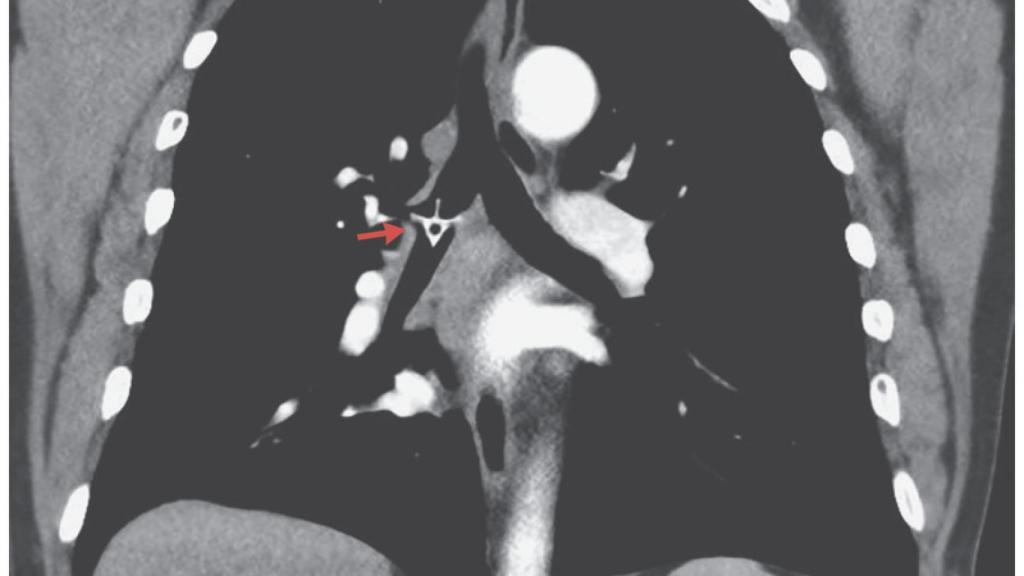

Imagen del hueso de pollo 'atascado' en el pulmón.

Imagen del hueso de pollo 'atascado' en el pulmón. NEJM

Sin embargo, tras el paso de cinco días, el hombre volvió de nuevo a urgencias: tenía fiebre, dificultad respiratoria y producía un sonido sibilante y agudo con cada respiración. Por ello, conociendo el dato de la visita anterior, los médicos que le atendieron le realizaron directamente un estudio de tomografía computerizada (TAC), en el cual sí se pudo vislumbrar un hueso de pollo en su bronquio derecho, la vía que une la tráquea con uno de los pulmones. El área donde se encontraba el hueso no dejaba pasar el aire correctamente, aunque no producía una obstrucción grave.